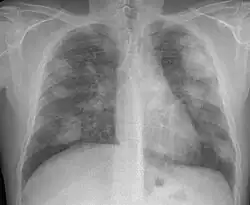

Xray of lungs

Xray of lungs, lighter patches visible

X-rays of patients with simple silicosis (top) and complicated silicosis (bottom)

According to a 2012 study published in Nature, there is a "positive exposure-response between silica and lung cancer".[49] Uranium mining produces silica-laden dust at a free silica rate of 5–15% in Bancroft, significantly less than the Elliot Lake mines which produced ore with 60–70% free silica.[32]: 36

In 1974, the Ontario Workmen's Compensation Board studied 15,094 people who worked in uranium mines in Bancroft and around Elliot Lake for at least one month, between 1955 and 1974. Of those 15,094 people, 94 silicosis cases were found in 1974, of which one was attributed to working a Bancroft mine, i.e. the other 93 were attributed to working in an Elliot Lake mine.[32]: 43, 62, 108

According to the Committee on Uranium Mining in Virginia, mines produce radon gas which can increase lung cancer risks.[50] Miners' exposure to radiation was not measured before 1958 and exposure limits were not enacted until 1968. Risks to miners at Bancroft and Elliot Lake mines were investigated and the official report of that investigation quotes a miner:[32]: 77

The aforementioned 1974 study of 15,094 Ontario uranium miners found 81 former miners who died of lung cancer.[32]: 79  Factoring in predicted lung cancer rate for men in Ontario led to the conclusion that by 1974 there were 36 more deaths than expected attributable to both Bancroft and Elliot Lake mines,[32]: 80  with the additional risk appearing to be twice as high for Bancroft miners compared to Elliot Lake miners.[32]: 348

A study report for the CNSC undertaken by the Occupational Cancer Research Centre at Cancer Care Ontario tracked the health of 28,959 former uranium miners over 21 years and found a two-fold increase in lung cancer mortality and incidence.[1]: 35 table 4  In an article published in The BMJ (journal of the British Medical Association) reported an increase of lung cancer risk; miners who have worked at least 100 months in uranium mines have a twofold increased risk of developing lung cancer.[51] The study is expected to be updated in 2023.[52]